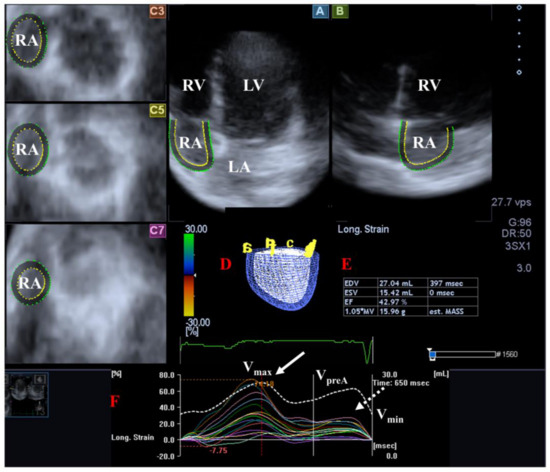

Figure 1.

Examination of the left ventricle (LV) by three-dimensional (3D) speckle-tracking echocardiography. Following echocardiographic data acquisitions, the following typical views are created: (A) Apical 4-chamber and (B) two-chamber longitudinal views and (C3,C5,C7) cross-sectional views at apical, midventricular and basal levels, respectively. LV can be easily detected alongside other heart cavities including the left atrium (LA) and the right atrium (RA) and ventricle (RV). A number of other details were also presented including (D) 3D cast and (E) end-diastolic (EDV) and end-systolic (ESV) volumes of the LV together with ejection fraction (EF) and mass of the LV and (F) curves representing changes in volumes and strains of LV over time. (F) Apical [white arrow] and basal [white dashed arrow] LV rotations and (G) radial, (H) longitudinal, (I) circumferential, (J) area and (K) 3D strains are also demonstrated.